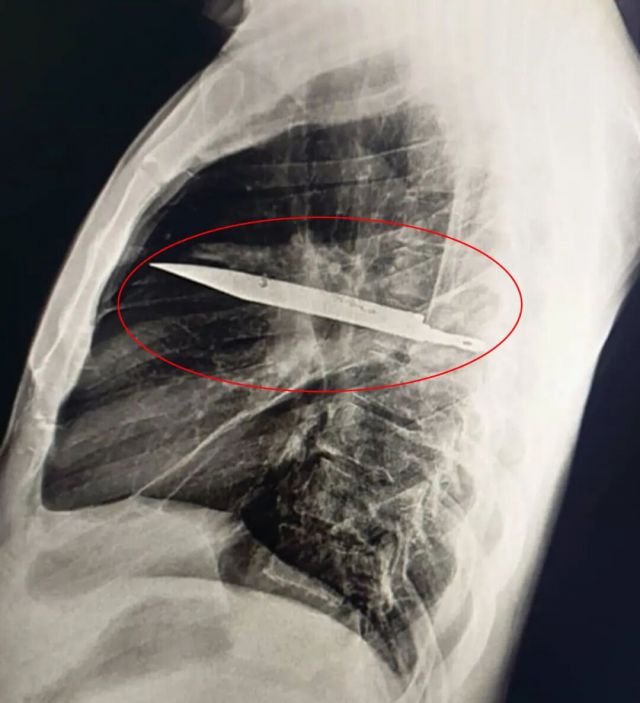

胸部X光检查结果让所有医生都大吃一惊——一把巨大的刀片竟然完整地插在患者胸腔内。影像显示,这把刀从右肩胛骨刺入,奇迹般地避开了所有重要器官。

外科医生在手术中小心翼翼地取出了刀片,同时清除了由坏死组织引起的脓液。患者在重症监护室观察了24小时后,被转至普通病房继续治疗10天。